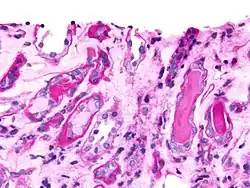

Epithelial cell casts

This cast type is formed by inclusion or adhesion of desquamated epithelial cells of the tubule lining. Cells can adhere in random order or in sheets and are distinguished by large, round nuclei and a lower amount of cytoplasm. These can be seen in acute tubular necrosis and toxic ingestion, such as from mercury, diethylene glycol, or salicylate. In each case, clumps or sheets of cells may slough off simultaneously, depending on the focality of injury. Cytomegalovirus and viral hepatitis are organisms that can cause epithelial cell death, as well.